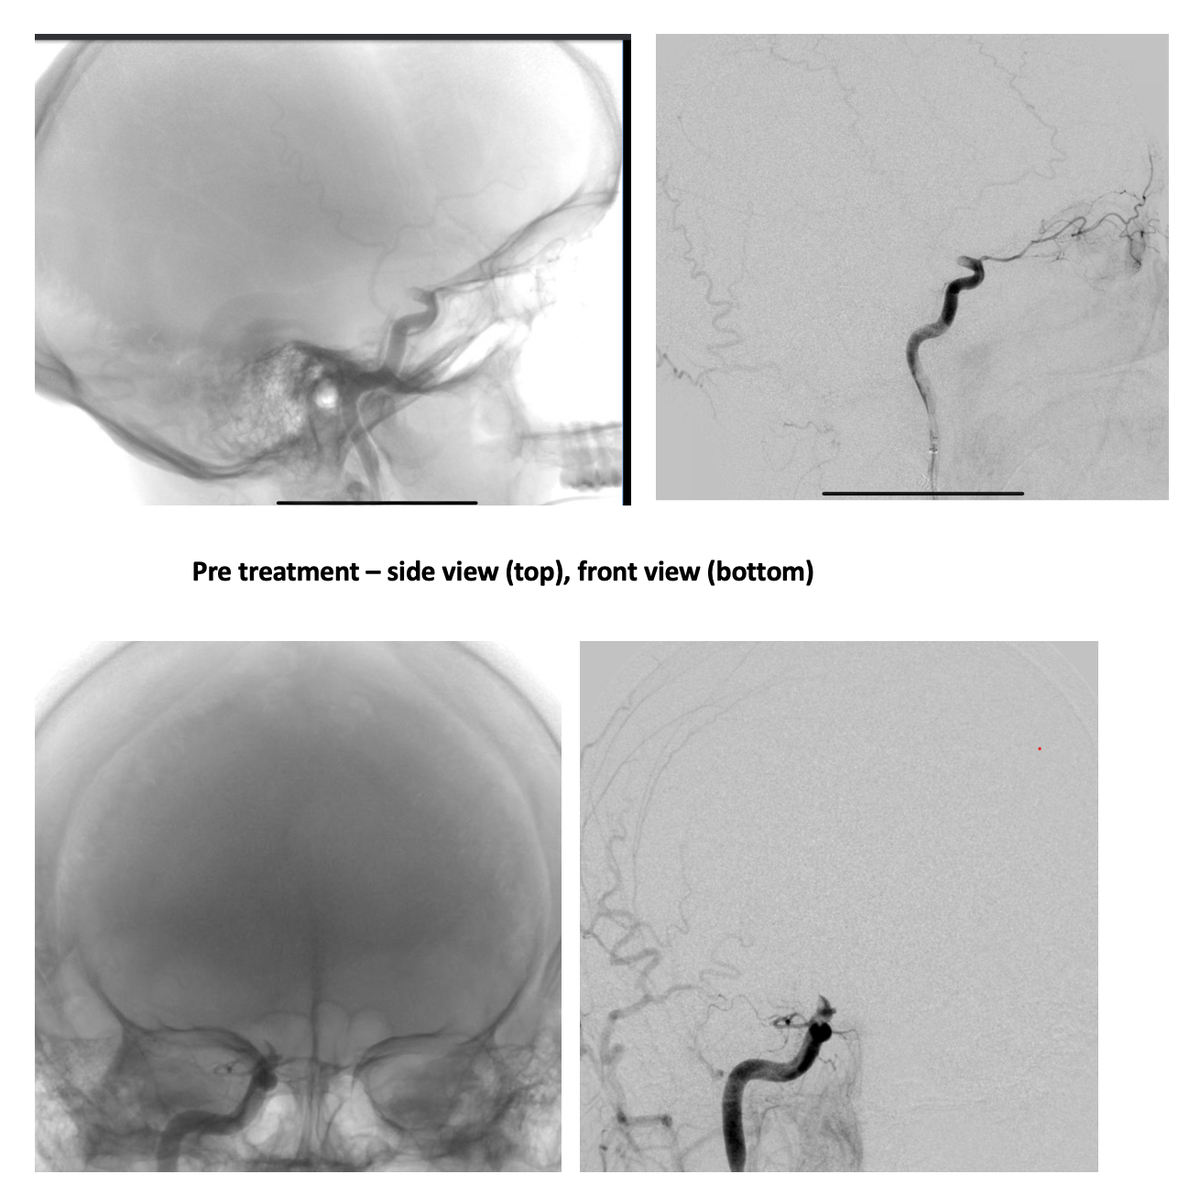

Στο Northwestern Memorial Hospital, όπου μεταφέρθηκε, ο Alex υποβλήθηκε σε ακτινογραφία, η οποία επιβεβαίωσε ότι είχε υποστεί εγκεφαλικό. Αυτό προκλήθηκε από θρόμβο που μπλόκαρε την κυκλοφορία του αίματος στη δεξιά πλευρά του εγκεφάλου. Ο 33χρονος χειρουργήθηκε άμεσα από τον επικεφαλής του τμήματος Νευροεπεμβατικής Ακτινολογίας, ο οποίος πραγματοποίησε μια ελάχιστα επεμβατική διαδικασία που ονομάζεται θρομβεκτομή και αφαίρεσε τον θρόμβο. Οι λειτουργίες του εγκεφάλου του Alex επανήλθαν στο φυσιολογικό αμέσως μετά τη διαδικασία.